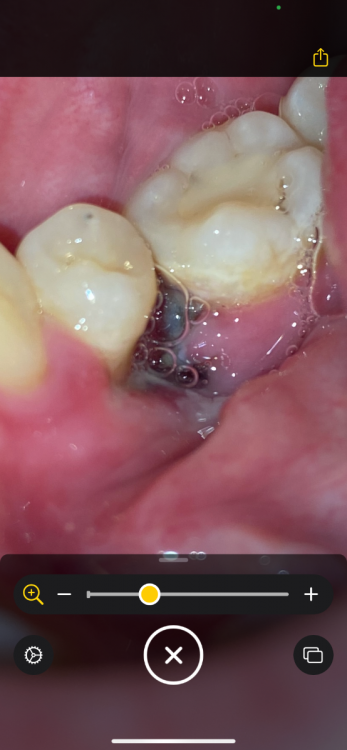

Здравствуйте.Удалили зуб в субботу, сегодня  вторник .Удаление было сложное.Сейчас из симптомов:постоянная пульсирующая боль,боль в ухе , опухшая щека,небольшое увеличение лимфоузлов. Была у врача который делал удаление в понедельник вечером.Посмотрел сказал , хотел залезть во внутрь,решил посоветоваться с другим врачом.и по совету другого врача не стал трогать. Оба молодых парня, почему то не очень вериться  , что это норма

3 и 5 фото как выглядит все сейч2B56CE66-56D0-4E1D-86A5-4E21849A5812.thumb.jpeg.abaa6f2b73e64da65817873712d3f05f.jpegE0B4CA80-B424-481A-84A3-CF3E12CB7724.thumb.jpeg.6413038171f373f539cc920d011ca1ae.jpegC7227F50-6100-4A26-A12F-E31C37F9D8B0.thumb.png.940d35b1a889de5ed43a9a7bb34ec48f.png1C299E13-97B5-4B9F-97A7-C54C58DB2369.thumb.png.14be377876310f3f10fa0a57b31c5ea7.png743AD060-C0D2-4F96-9EFE-2BF3908D1153.thumb.jpeg.593d27327ab5e07b3e1f53754b9b9614.jpegас

Антисептические ванночки,аппликации с гелем "Метрогил-Дента" на лунку. Пока там есть сгусток ,если же сгусток разрушится ,надо будет вымывать еду шприцем с обломанной иглой из лунки и вводить туда тот-же гель "Метрогил-Дента" Я не пойму по снимку - там участок кости оголён у Вас с язычной стороны или там всё мягкое?